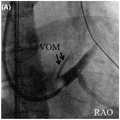

With reference to fig. 12, since the VOM is the remnant of the embryonic venous sinus and left major vein, it contains adipose and fibrous tissue, blood vessels, fascicles, nerve fibers and ganglia. Under traditional radiofrequency ablation energy, the conduction effect of fat to heat energy is poor, and the fascicles in the VOM can not be damaged completely, so that the ablation effect of radiofrequency ablation on the fascicles in the VOM is unsatisfactory, and the problem of fat separation can not be solved by the existing radiofrequency ablation technology. The diameter of the traditional radio frequency ablation catheter is between 2 and 3mm, while the VOM is often very narrow, the diameter is less than 2mm, and the radio frequency ablation catheter can not reach the interior of the VOM generally.

Fig. 12 is a diagram of a background art VOM medical imaging.